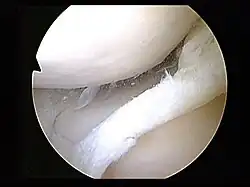

Tear of medial meniscus